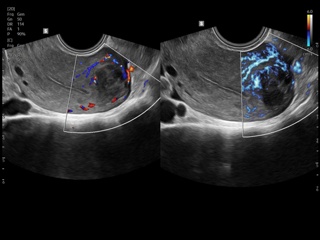

Atlas of ultrasound images - obsterics

In the section "Оbsterics" of atlas the results of ultrasonic examinations of pregnant women with different durations of gestation are represented. Here you can see images of internally organs, cerebrum, cordis and the sex of the fetus, the sonograms of multiple pregnancy, the blood flow in placenta and umbilical cord, defects of fetal`s development, etc.